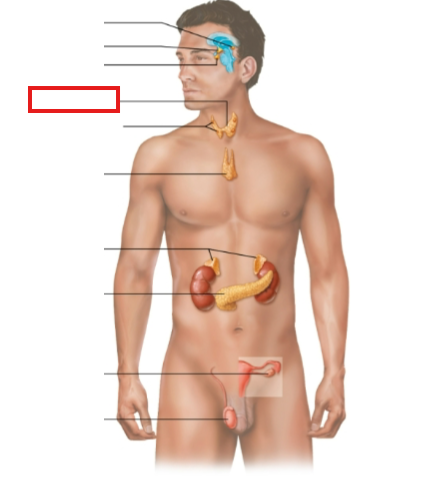

What structure is highlighted?

pineal gland

hypothalamus

pituitary gland

thyroid gland

parathyroid glands

thymus

adrenal glands

pancreas

ovary (female)

testes (male)